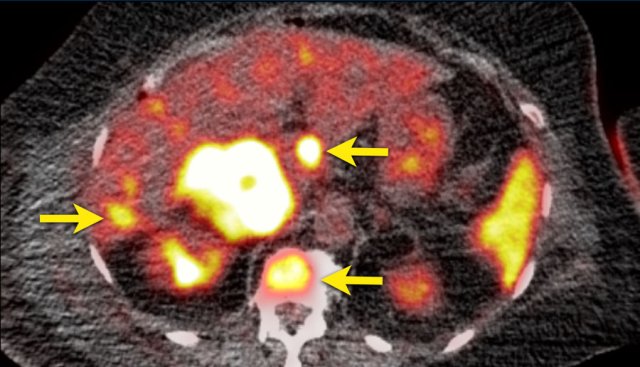

The axial venous phase CT on the left shows a large inhomogeneously enhancing right adrenal lesion with a small cyst, which could not be diagnosed as an adenoma with CT washout, making it an indeterminate lesion.

The plasma free metanephrines were elevated and the lesion was diagnosed as a pheochromocytoma.

MIBG SPECT for staging showed intense uptake in only the right adrenal gland.

PET-CT was also performed, which in contrast showed uptake only slightly higher than normal liver.

This is highly unusual for pheochromocytomas, which are usually very FDG-avid, even when they are benign.

If the primary tumor lacks FDG uptake, the sensitivity for finding metastases on an FDG PET-CT will be very low.